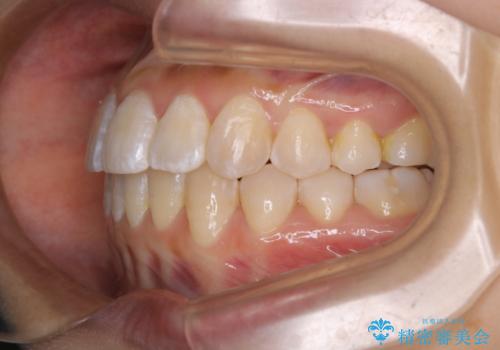

前歯のがたつきとオープンバイト:インビザラインでまとめて治す

- 噛み合わせと、前歯のがたつきが気になるとご相談にいらした方です。インビザラインFULLで綺麗な歯並びと噛み合わせを作ることが出来ました。

オープンバイトの方への治療は、通常抜歯を行いワイヤーによる矯正治療を行うことが多いですが、今回はインビザラインの特性を生かし、非抜歯にて綺麗な歯並びを作ることが出来ました。

舌癖がある方は、歯を内側から押し出す力が日常的に働くため、矯正治療後も歯と歯の隙間が開いてしまうなどの後戻りのリスクが高いことが知られています。舌の正しいポジショニングやお口周りの筋肉のトレーニングを行うことで後戻りのリスクを減らすことが可能です。